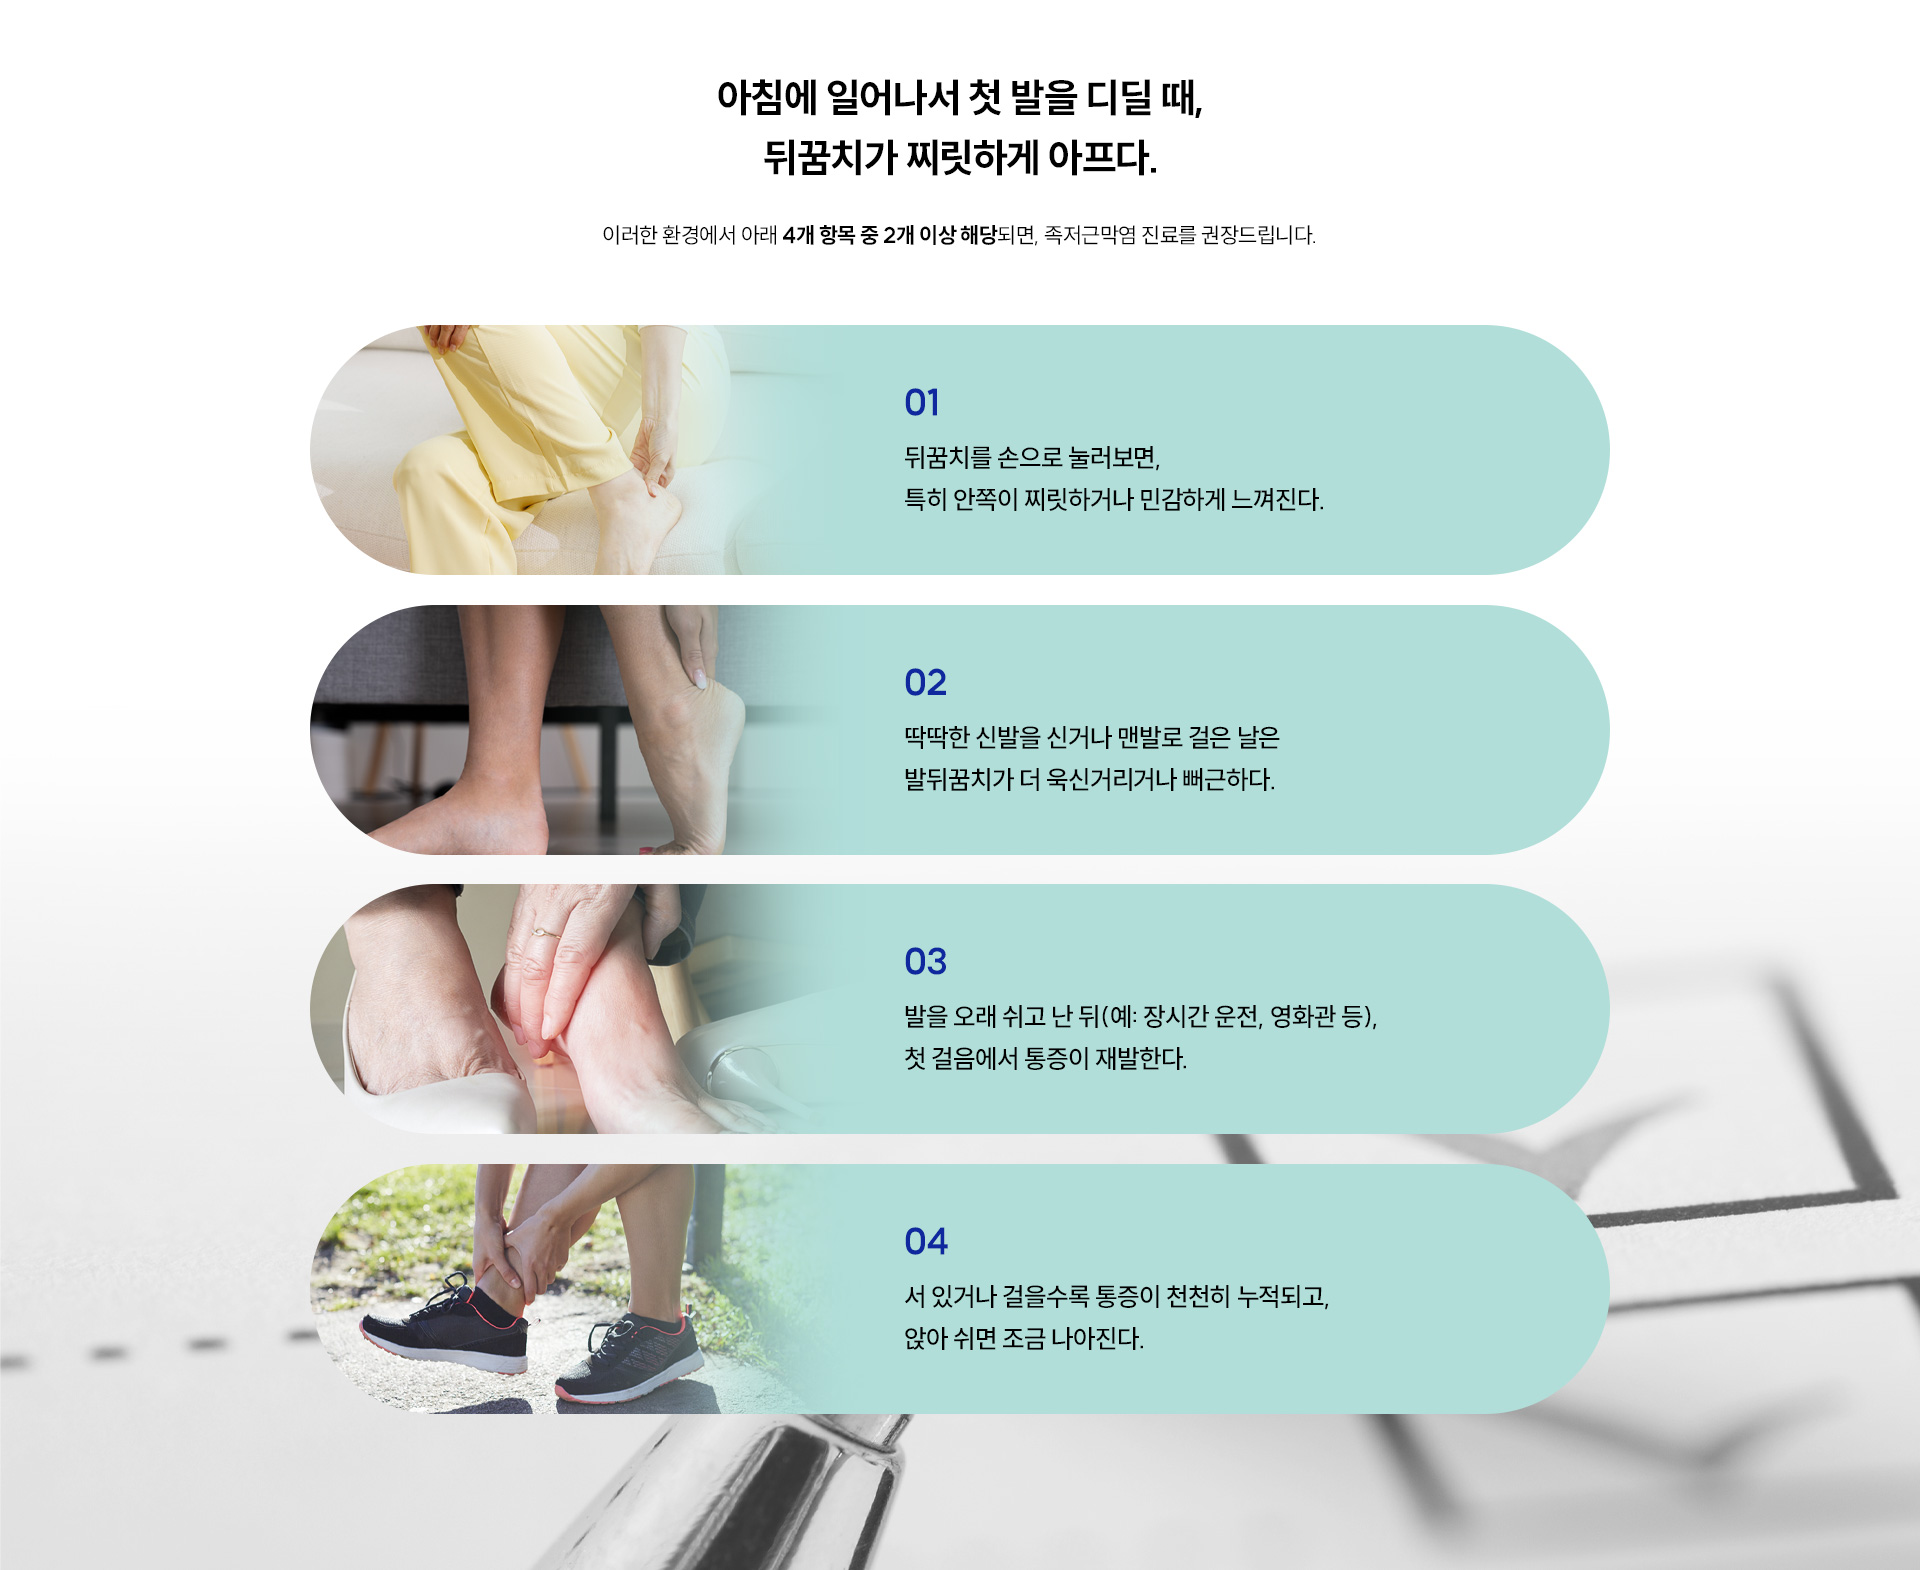

아침에 첫 발을 내디딜 때 발바닥에 찌릿한 통증이 느껴진다면, 족저근막염을 의심해볼 수 있습니다.

서 있거나 걸을 때 통증이 빠르게 심해지는 것도 특징 중 하나입니다.

이 질환은 치료를 미루면 쉽게 낫지 않고 만성 통증으로 이어질 수 있기 때문에, 초기 대응이 매우 중요합니다.

족저근막염으로 인해 발생할 수 있는 통증이나 질환들은 아래와 같습니다.

· 뒤꿈치 뼈 돌기(골극, Heel Spur)

: 족저근막에 염증이 오래 지속되면, 뒤꿈치 뼈에 돌기가 자라며 날카롭고 찌르는 듯한 만성 통증을 유발할 수 있습니다.